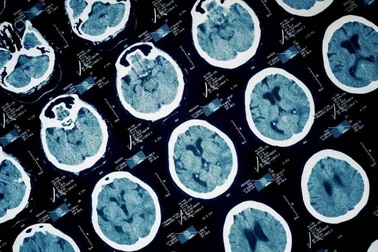

Bác sĩ chẩn đoán sai, bệnh nhân u màng tủy suýt liệtCác ngón bàn chân trái có biểu hiện căng cứng, đi lại khó khăn, bệnh nhân nhiều lần được bác sĩ chẩn đoán và điều trị căng cơ, đau thần kinh tọa nhưng tình trạng ngày càng nặng. Người bệnh may mắn thoát khỏi nguy cơ bại liệt khi bác sĩ phát hiện bệnh lý u màng tủy.